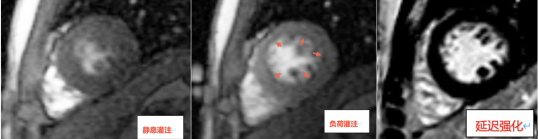

检查发现患者静息灌注未见异常(图1A),负荷灌注其左心室多节段可见心内膜下灌注缺损(图1B),延迟强化未见异常(图1C),提示患者心肌存在微循环障碍,这也解释了患者心外膜冠状动脉主要分支未见明显狭窄,仍反复出现胸闷心悸等症状的原因。小陈有糖尿病及高血压基础病,导致心肌微循环障碍,故治疗上予改善心肌微循环。

图1A 图1B 图1C